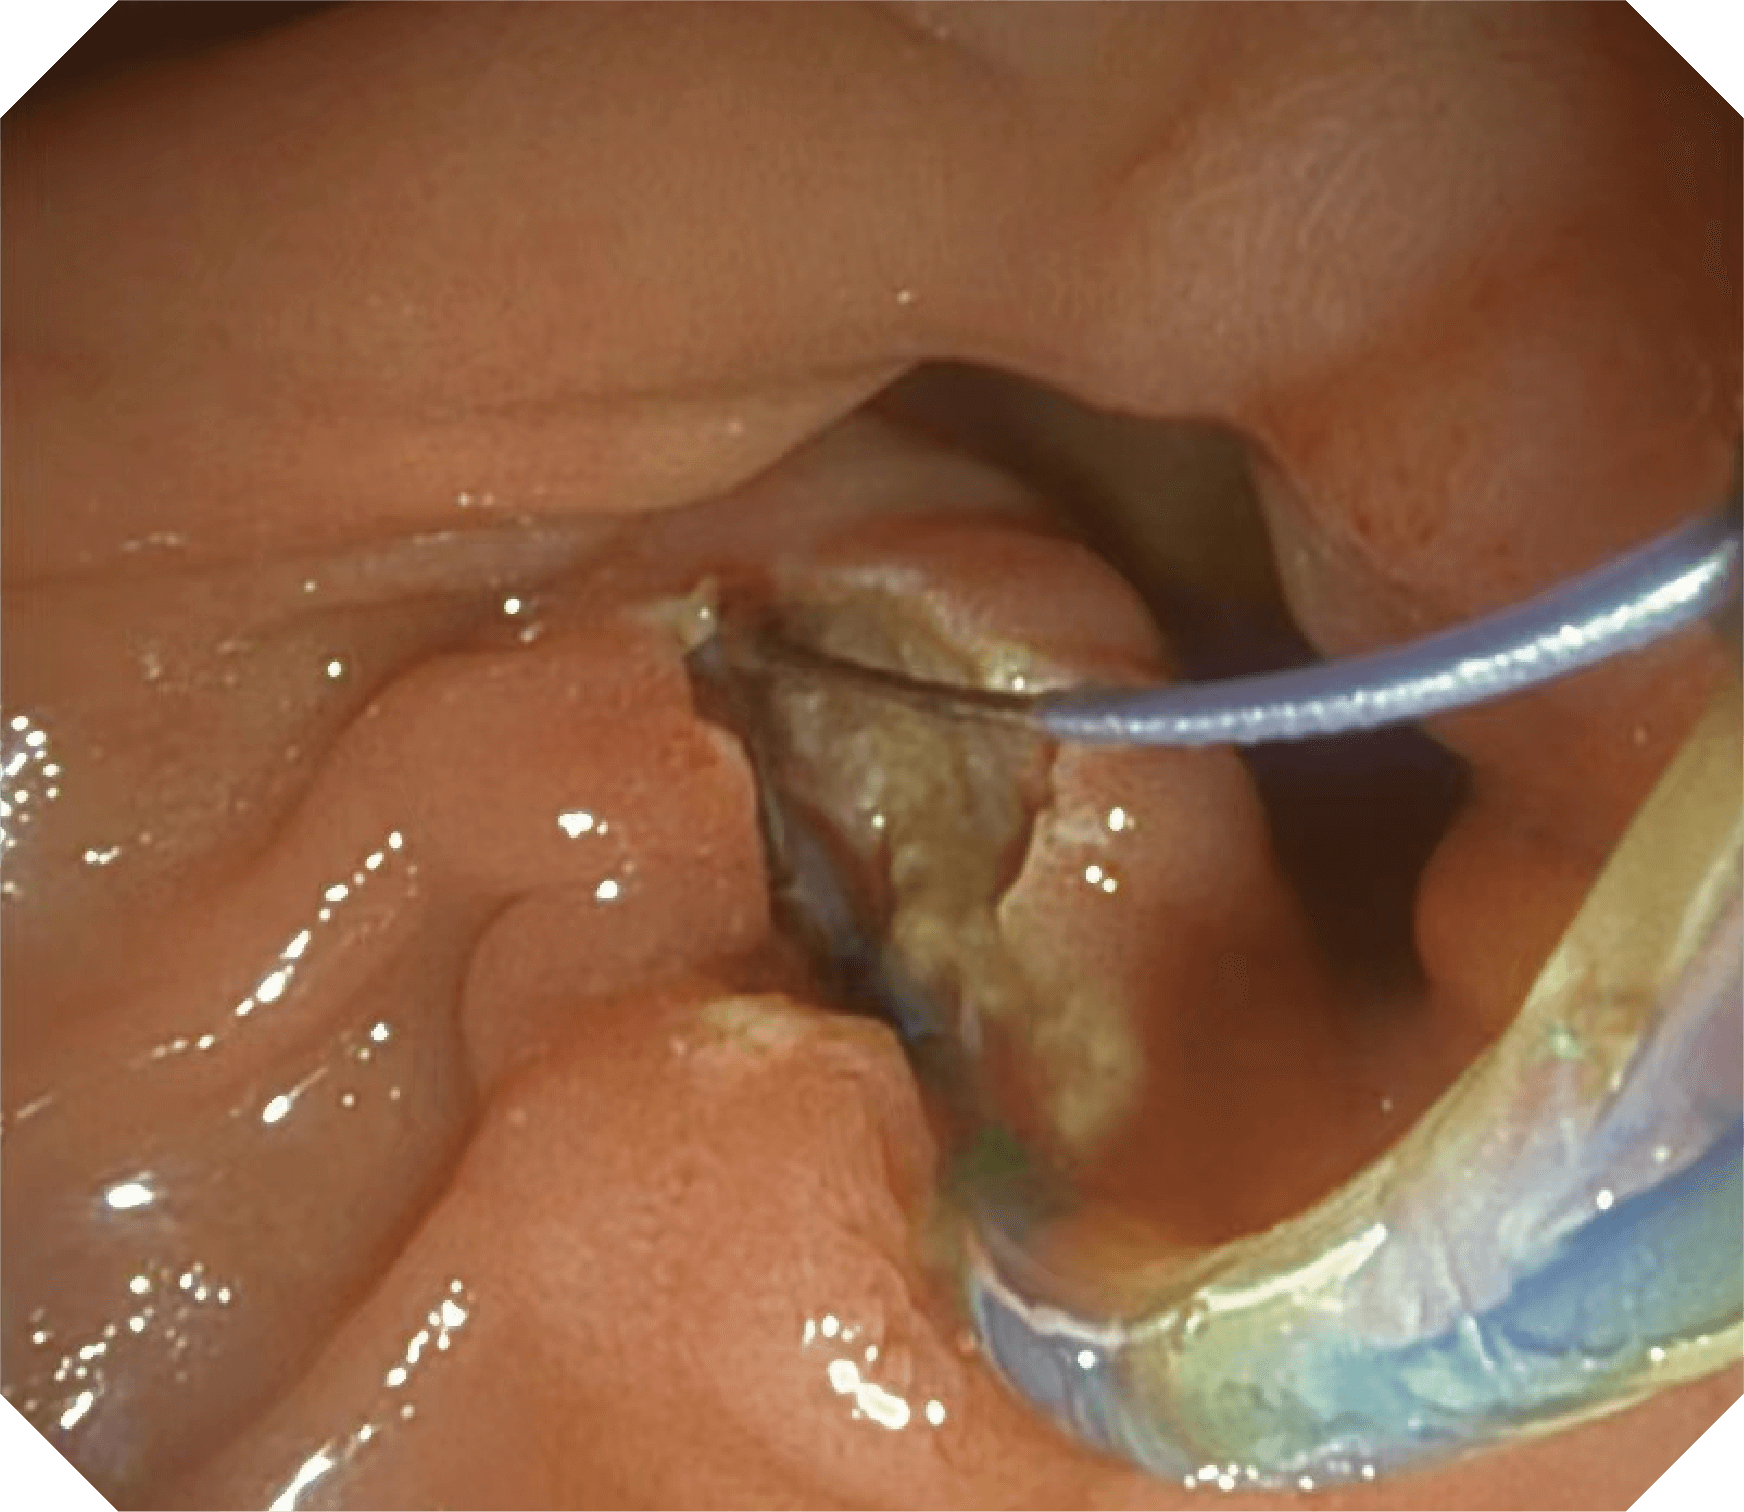

导丝机械锁紧功能

V槽设计提升导丝控制

更好的通过性,更稳定的镜体支撑力